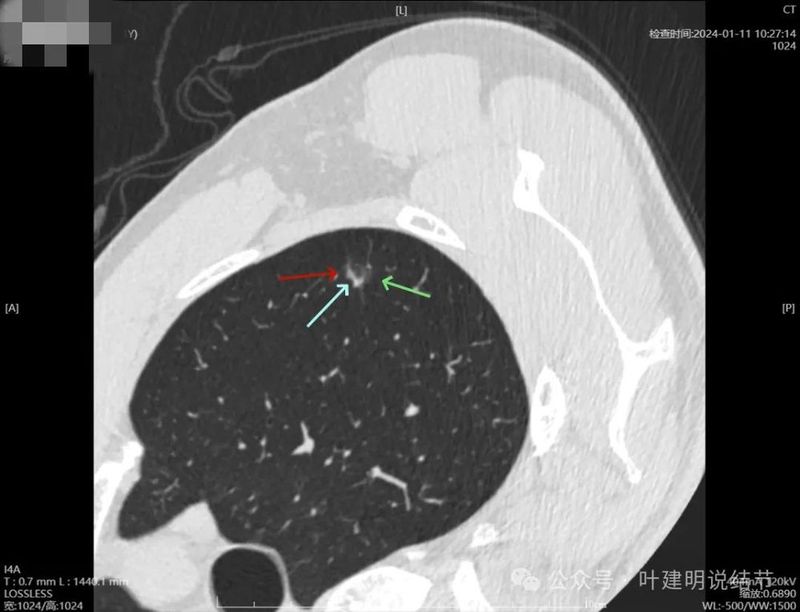

2024年1月靶重建:

病灶密度较高,有月牙铲征,轮廓显模糊。

有微小血管,密度较高,有偏实性成分,磨玻璃密度淡,边界稍糊。

似乎密度过高,毛刺不是太锐利。

密度太高,而且偏长条状。

边缘区密度高,条状。

实性部分密度过高,磨玻璃部分密度淡且瘤肺边界不太清。